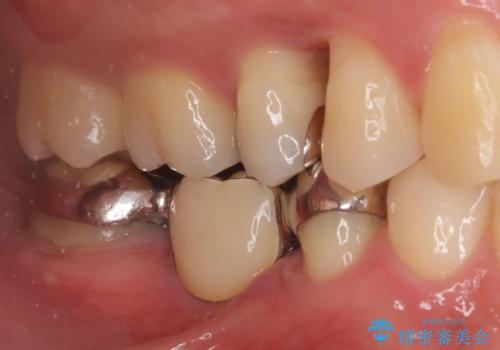

右下奥歯の5・6・7番に装着されていたブリッジの不具合を主訴にご来院されました。ブリッジは汚れが溜まりやすく、土台となる歯への負担も大きいため、今回は「それぞれの歯を独立させて、自分の歯を長持ちさせたい」というご希望に合わせ、以下の計画を立案しました。

ブリッジを外し、欠損している6番にインプラントを埋入。

土台となっていた5番と7番は、セラミッククラウンで修復。

インプラントとセラミック修復: 中央の6番にインプラントを埋入し、両隣の5番・7番はそれぞれ独立したセラミッククラウンで修復しました。ブリッジ時代は歯がつながっていたためお手入れが困難でしたが、個別の歯になったことで、一本ずつフロスが通るようになり、セルフケアの精度が劇的に向上しました。